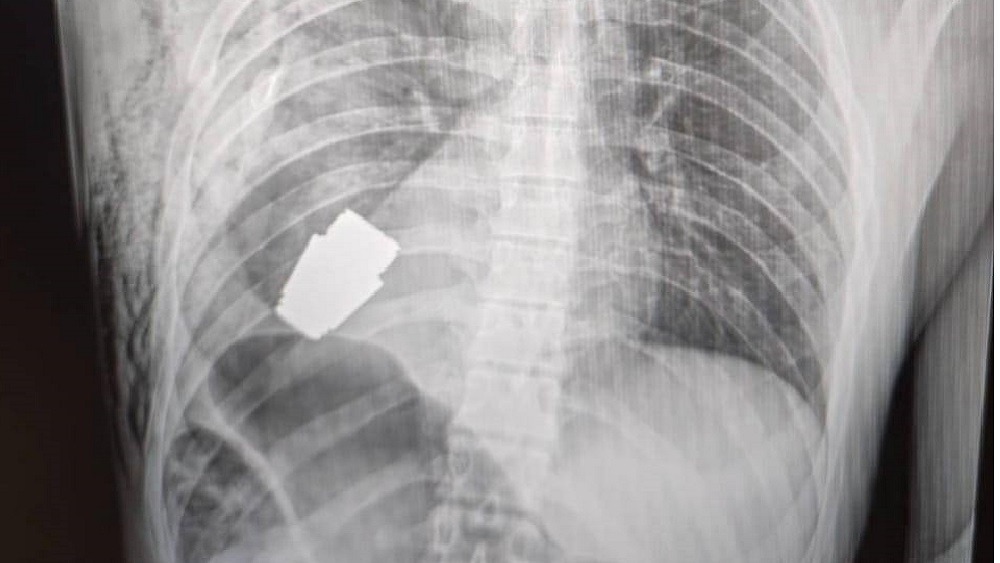

Військові лікарі з тіла війсковослужбовця видалили гранату ВОГ(постріл гранатометний ВОГ-25, – ред. ) Ситуація ускладнилася тим, що граната не розірвалася. Постріл було видалено у присутності двох саперів, які страхували безпеку медичного персоналу. Про це у своєму Телеграмі повідомила заступниця міністра оборони України Ганна Маляр.

Операція проводилася одним з найдосвідченіших хірургів ЗСУ — Андрієм Вербою без електрокоагуляції. Такий спосіб було обрано хірургом виключно через те, що граната могла здетонувати в будь-який момент. Оперативне втручання пройшло успішно. Наразі пораненого військовослужбовця скеровано на реабілітацію.